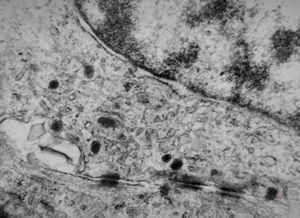

M,3m. | surfactant